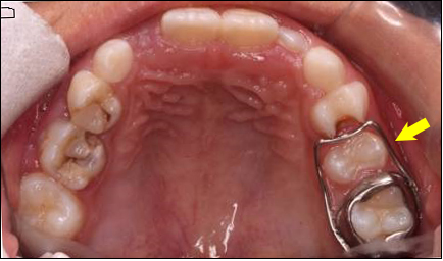

如果像这张图中展示的继承恒牙已经萌出,但间隙保持器尚未脱落,请尽快到医院就诊取下间隙保持器。

否则,恒牙可能会长歪,或因为食物嵌塞而患龋。